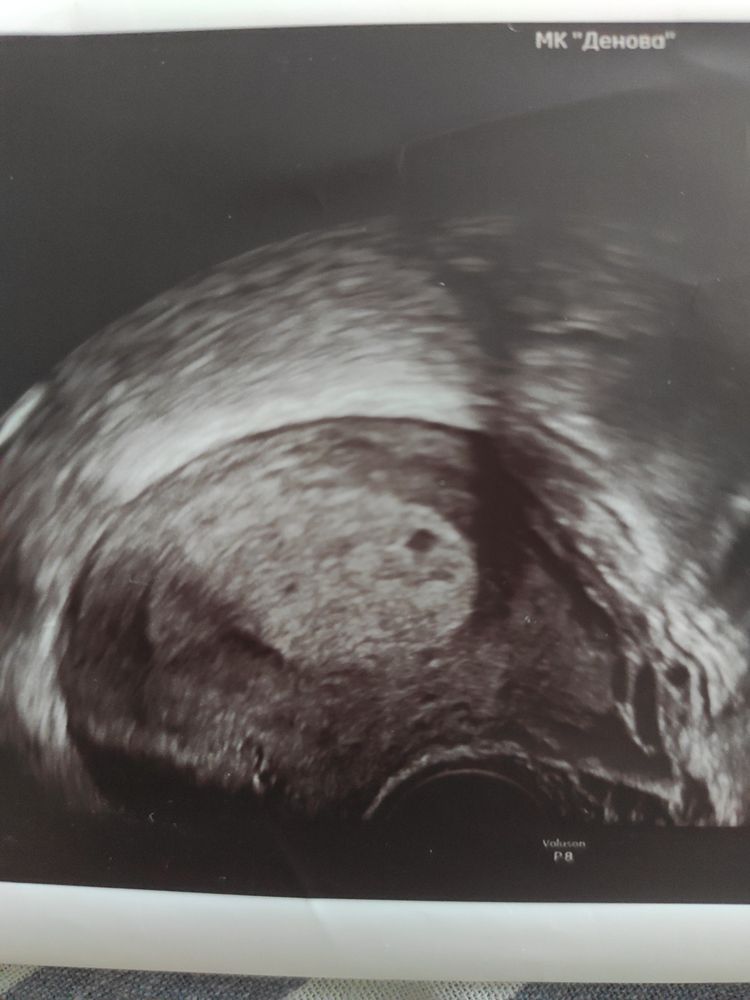

(фото узи прилагаю)

была на узи (тк знаю ,что после хгч 1.500 уже модно увидеть ПЯ)

По фото не определить размер,но думаю все соответствует вашему сроку,так как размер пя зависит от уровня хгч,у вас хгч хороший и по сроку,у меня в одну беременность на 21 дпо хгч 1990 УЗИ на 22 дпо пя 7 мм и никто не говорил,что оно не соответствует сроку,все по сроку было

1) а размеры то какие не понравились врачу? На вид там даже желточный мешок уже есть.